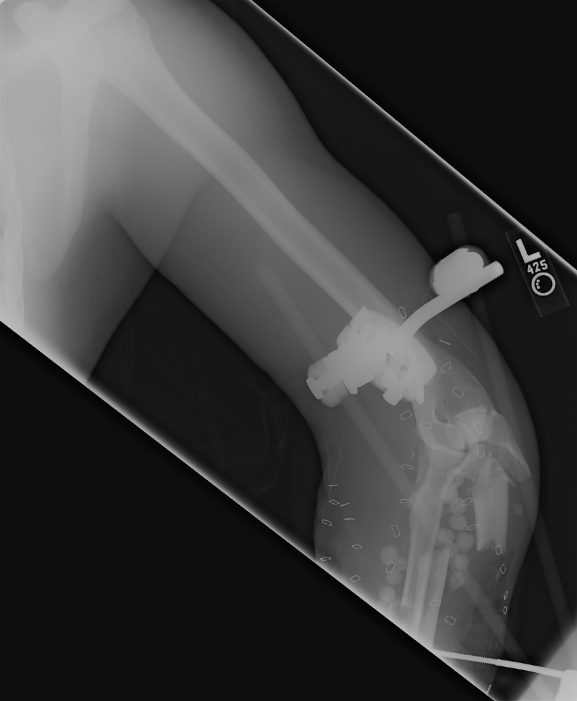

Nov 23, 2007 These pictures were taken in Iraq or possibly in Germany. The stabilizing bars have been attached above his elbow and about half way down his forearm. You can see the bone chips scattered around in his upper forearm. |